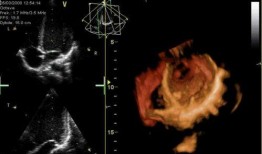

心脏跳动视频,揭秘心脏跳动的奥秘

你知道吗?最近在网上看到一个超级神奇的视频,简直让人心跳加速!就是那种心脏跳动的视频,感觉就像是在你的胸腔里亲自感受一样。今天,...